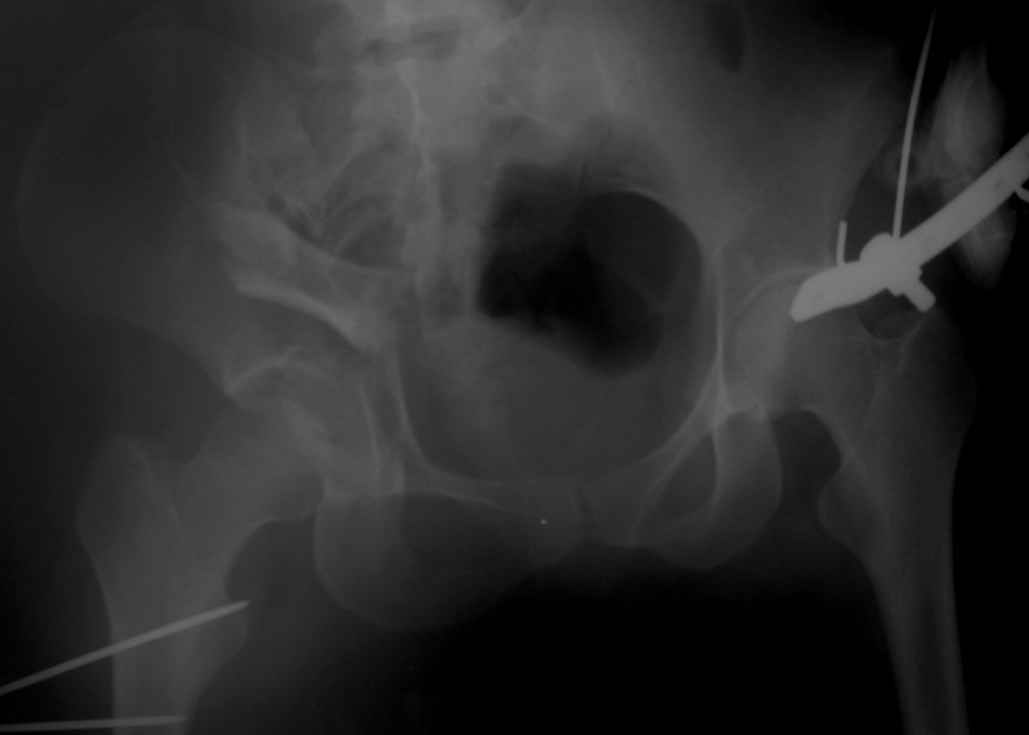

Вот еще одно наблюдение не совсем частое, большое желание поставить распорку поперек таза, чтобы вернуть конфигурацию тазового кольца.

Но считаю, что третий сорт не брак, тем более-то ноги одинаковые. Доступ между подвзлошно-паховым и подвздошно-бедренным, пришлось несколько расширяться книзу, но внимательно не посмотрел и попал на бедро, надо было все-таки по паховой складке, но вот беда - на хорошо загорелом теле не нашел следов более светлой кожи, поэтому рубец будет несколько выступать из под бикини. Посылаю три снимка. Пока. Вернусь через 10 дней. Жду ответа. ЛАФ.